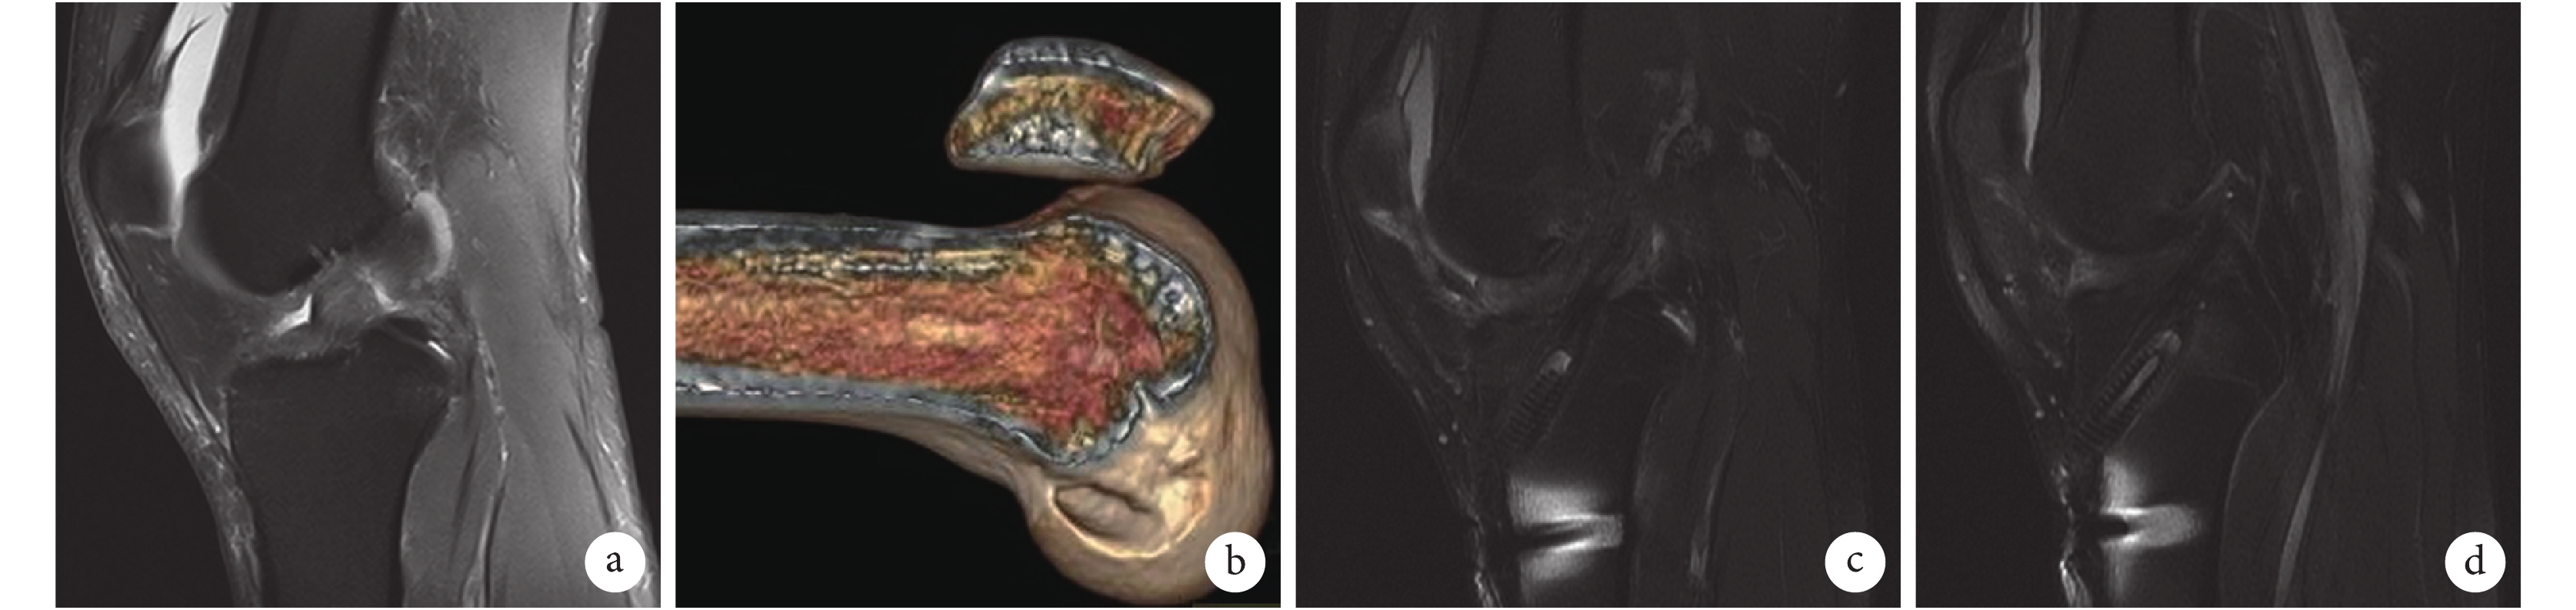

術后 1 d 三維 CT 檢查示兩組股骨及脛骨隧道均位于 ACL 止點印跡內。MRI 復查兩組均無移植物斷裂及明顯松弛發生。術后 6 個月兩組移植物中、遠端 SNQ 差異無統計學意義(P>0.05);近端 A 組明顯低于 B 組,差異有統計學意義(P<0.05)。術后 12、24 個月 A 組移植物近、中、遠端 SNQ 均低于 B 組,差異有統計學意義(P<0.05)。見表 2 及圖 3。

a. 術前 MRI;b. 術后 1 d 三維 CT;c. 術后 6 個月 MRI;d. 術后 24 個月 MRI

Figure3. A 27-year-old male patient with left ACL rupture in group Aa. Preoperative MRI; b. 3D-CT at 1 day after operation; c. MRI at6 months after operation; d. MRI at 24 months after operation